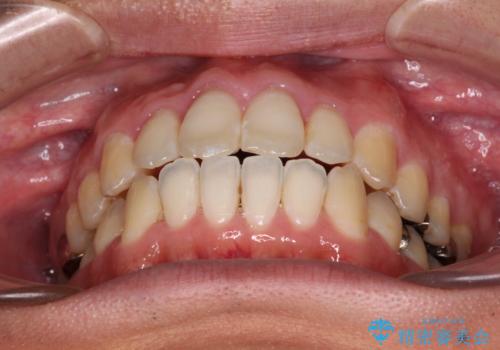

上顎歯列全体を後方に移動させたため、口元の突出感も改善され、装置を外してからは口が閉じやすくなりました。

また、上下犬歯が接触するようになったため、奥歯にストレスのかからない歯ぎしりができるようになり、顎の疲れも改善されました。